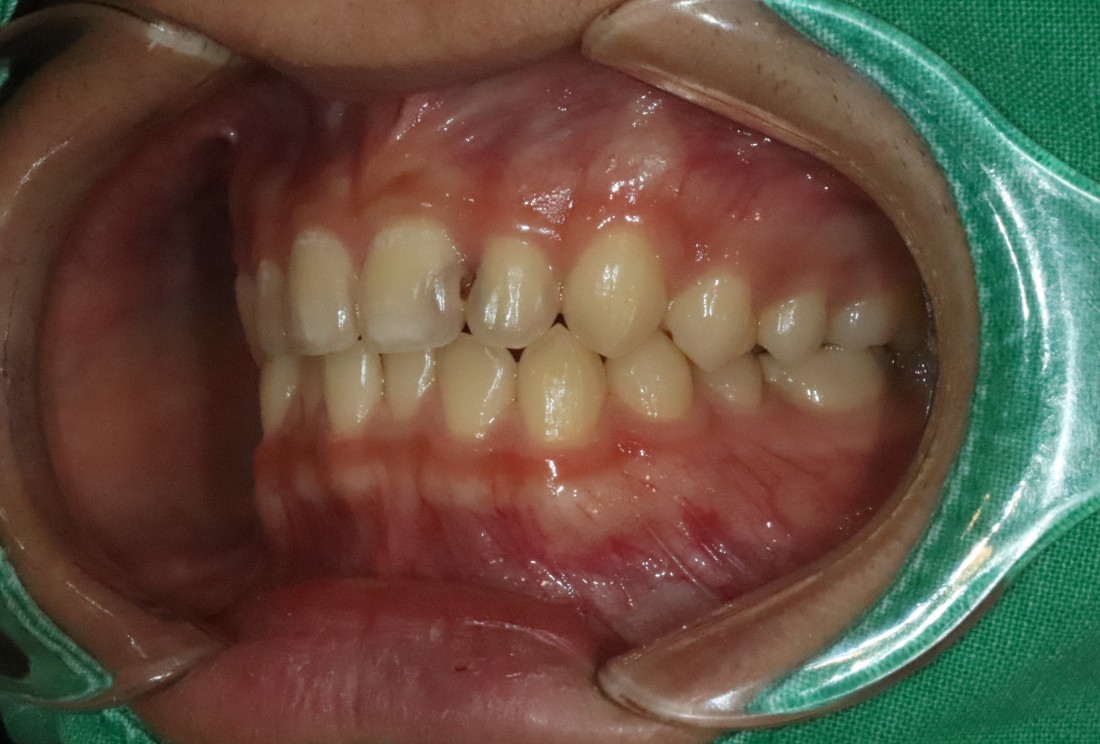

광주 라미네이트를 추천하는 분들은

앞니 컴플렉스가 심하신 분들인데요.

충치로 인해 치아색이 변색되거나

앞니 모양을 고르게 하고 싶으신 분들,

앞니가 벌어진 경우,

치아 크기가 다른 왜소치,

누렇게 변색된 치아 등

다양한 앞니 컴플렉스의 경우에

광주 라미네이트 진료로

환한 미소를 완성할 수 있습니다.